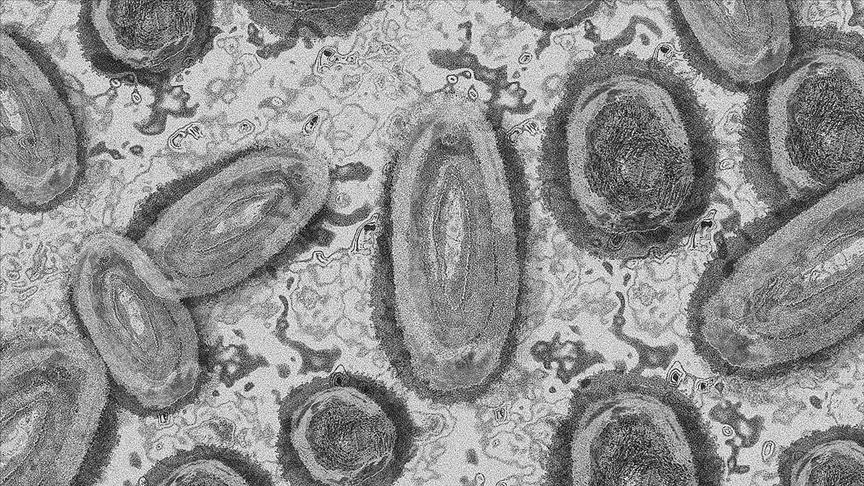

Bulgaristan'da ilk maymun çiçeği vakaları tespit edildi

Bulgaristan Sağlık Bakanlığı ülkede ilk kez, iki kişide maymun çiçeği virüsünün tespit edildiğini duyurdu.

Bakanlıktan yapılan yazılı açıklamada, 41 ve 44 yaşındaki iki erkeğin tanısının kesin olduğu bildirildi.

Açıklamada, maymun çiçeği virüsü tespit edilen söz konusu iki kişinin başkent Sofya'da farklı hastanelerde tedavi gördüğü belirtildi.

Bu kişilerin daha önce İspanya ve İngiltere'yi ziyaret ettiğini aktaran yetkililer, hastaların durumunun iyi olduğunu açıkladı.